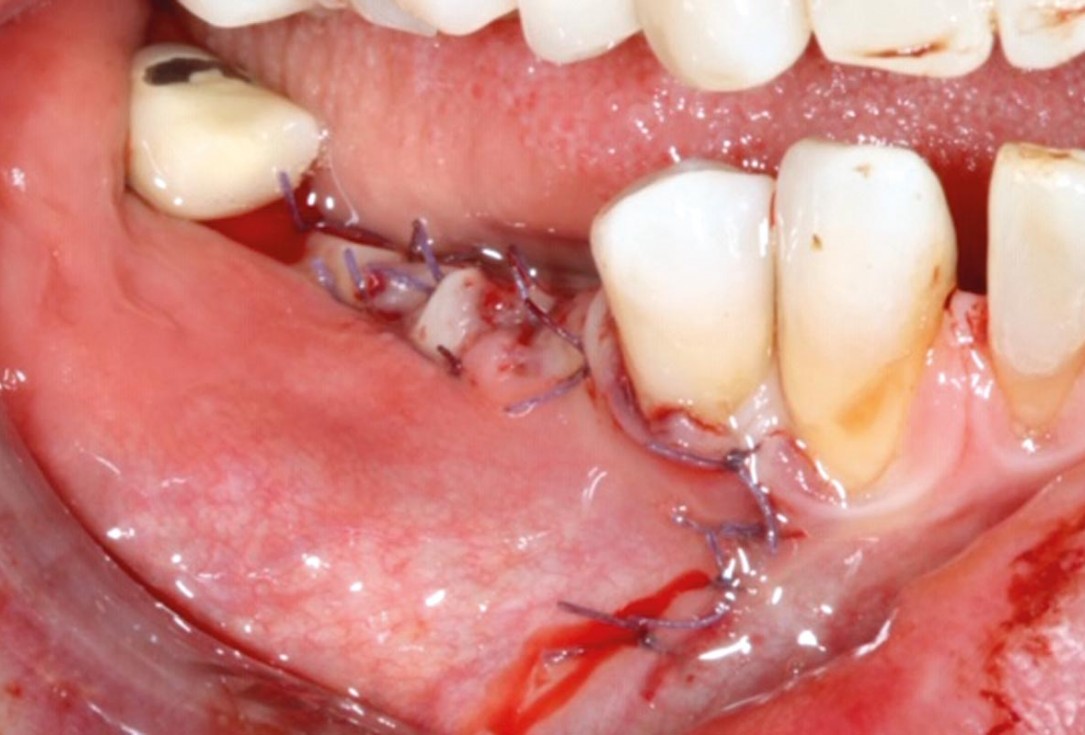

3/10 - Jason membrane® positioned and fixed.GBR with cerabone® and Jason® membrane DentalPro - Dr. A. Gargiulo

6/10 - Jason® membrane repositioned and sutured.GBR with cerabone® and Jason® membrane DentalPro - Dr. A. Gargiulo